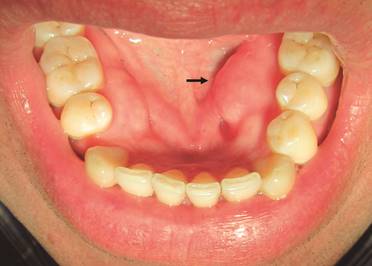

En la familia estudiada, el sujeto III.2, 46 años, los aumentos de volumen mandibulares diagnosticados previamente como torus mandibular atípico, son más compatibles con el diagnóstico de osteoma principalmente al considerar su comportamiento clínico: crecimiento asimétrico, indoloro, lento y continuo en el tiempo (Fig. 3).

En la familia estudiada, tanto el sujeto III.2, 46 años, que presentó osteomas, comoel sujeto III.1, 47 años,que presentó un odontoma compuesto, no asistieron a la evaluación por gastroenterólogo para realización de colonoscopía y evidenciar presencia de poliposis colónica en el tiempo de duración del estudio, sin confirmar el diagnóstico de PAF.A pesar de la edad de los pacientes (46 y 47 años) y antecedentes familiares de PAF, es importante realizar el examen intestinal para descartar la existencia de PAF atenuada que tiene un curso más leve que la PAF clásica con el desarrollo de menos número de pólipos y desarrollo tardío en la edad de cáncer colorrectal4,6.

La condición de Fordyce encontrada en el sujeto III.2 se ha asociado alSíndrome de Lynch, y su variante Síndrome de Muir-Torre1.La presencia de tags mucosos se han descrito principalmente en enfermedad de Crohn12; Sin embargo, esta excrecencia mucosa en el frenillo labial encontrada en sujeto III.1, III.2 y III.5 (fig.4), ha sido identificada comoapéndice del frenillo vestibular, un fragmento de tejido mucoso que se desprende desde el frenillo labial del maxilar de herencia autosómica dominante13. Éstos no han sido descritos como manifestaciones orales asociadas a PAF.